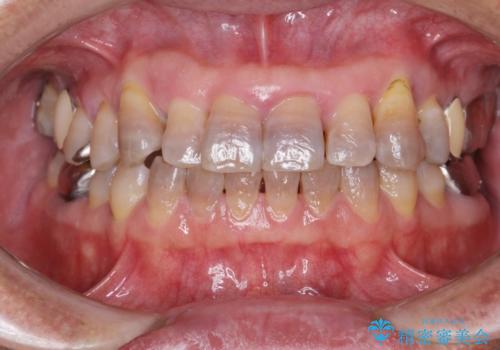

- 他院で上顎は全て抜歯し、入れ歯にする必要があると言われ相談に来院されました。

検査の結果、重度の歯周病であることから保存が難しい歯は抜歯を行いインプラントを、残すことが可能な歯には再生治療を含めた歯周病治療を行いより多くの歯を残す歯周病治療を計画します。

上顎は、残っている前歯も揺れがあり残すためにはクラウンでつなぐ歯周補綴が必要な状態です。